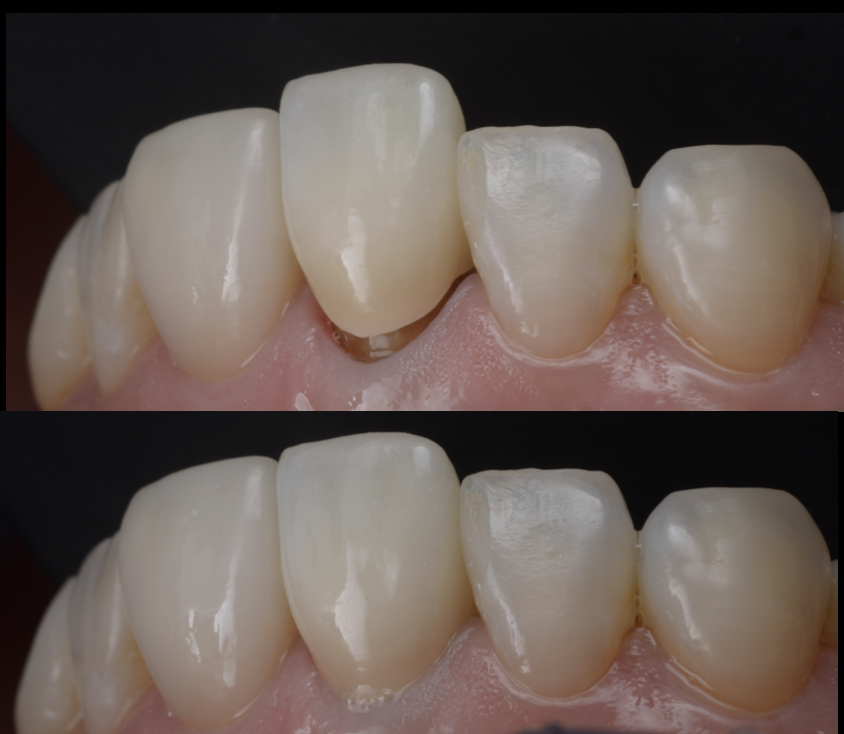

医院ブログ2025.09.18

池袋でインナーブリーチ|前歯の神経を失った歯の...